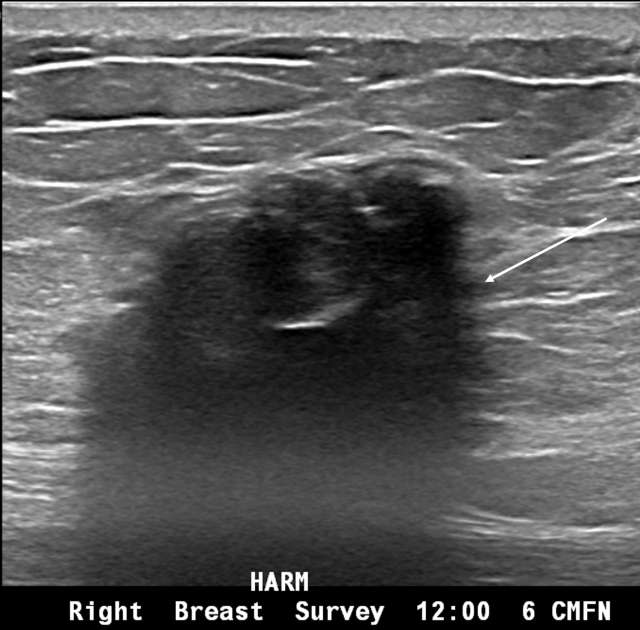

Irregular mass in the breast with punctate echogenic foci

Figure 2. Irregular mass in the breast with punctate echogenic foci (arrow). This mass was biopsied, which turned out to be invasive ductal carcinoma.